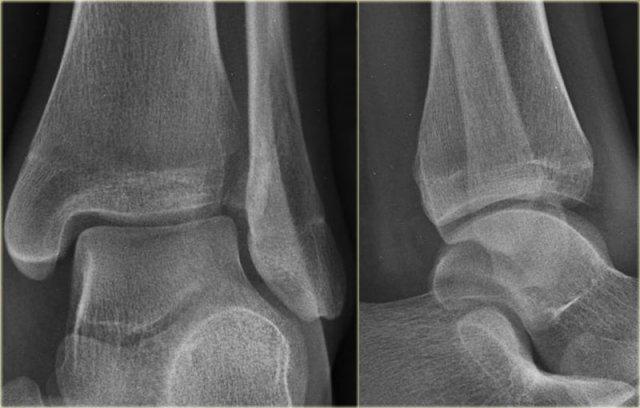

Bệnh nhân này bị lật cổ chân và bất thường duy nhất được thấy trên tư thế nghiêng.

Tổn thương này được cho là bong điểm bám mắt cá sau.

Biết rằng đây có thể là dấu hiệu duy nhất của gãy Weber C cao, các phim X-quang bổ sung đã được chụp.

Tiếp tục xem hình ảnh cẳng chân.

Có thể thấy một đường gãy xương mác cao kín đáo (mũi tên).

Chẩn đoán cuối cùng là gãy Weber C hoặc theo phân loại Lauge Hansen: chấn thương xoay ngoài – sấp giai đoạn 4.